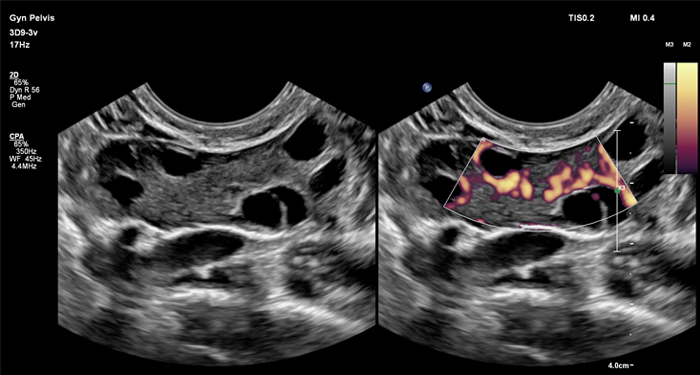

At the touch of a button, the new MaxVue high-definition display brings extraordinary visualisation of anatomy with 1,179,648 additional image pixels compared to a standard 4:3 display format mode. MaxVue enhances ultrasound viewing during interventional procedures and provides 38% more viewing area to optimise the display of dual, side/side, biplane, and scrolling imaging modes.